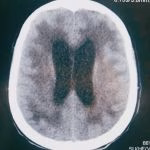

- Hematomas cerebrais

- Hemorragia subaracnóidea

- Hematoma subdural crônico

- Drenagem de hematoma